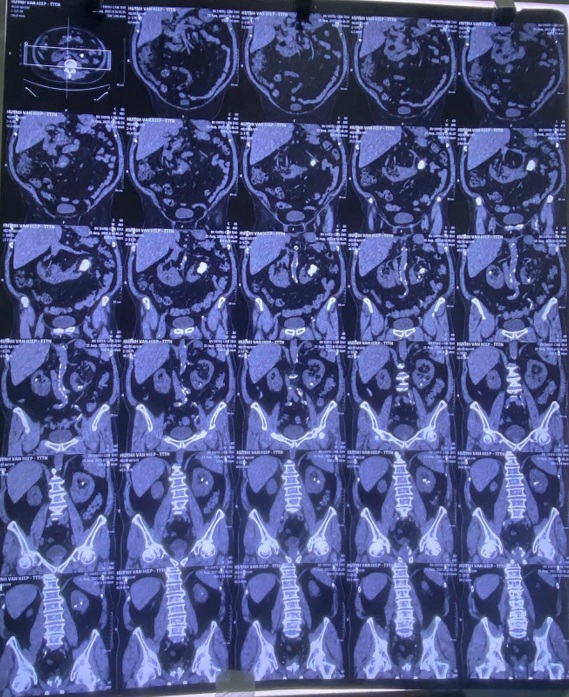

Qua thăm khám và chẩn đoán hình ảnh, các bác sĩ xác định bệnh nhân bị sỏi san hô thận trái sỏi nhỏ thận phải trên nền thận dị dạng bẩm sinh – gọi là thận móng ngựa. Đây là tình huống phức tạp vì thận móng ngựa có cấu trúc giải phẫu khác thường, khiến việc phẫu thuật lấy sỏi khó khăn hơn nhiều so với bệnh nhân thận bình thường.

Sau khi hội chẩn, bệnh nhân được chỉ định lấy sỏi thận qua da bằng đường hầm nhỏ (mini-PCNL) đối với sỏi san hô ở thận trái. Kíp phẫu thuật gồm ThS.BS Đặng Hoàng Minh, ThS.BS Lê Thanh Bình, ThS.BS Dương Văn Huynh và BS Tô Ngọc Đăng Khoa. Ca mổ kéo dài khoảng 3 tiếng với nhiều thử thách nhưng đã diễn ra thuận lợi.

Kết quả: sỏi được lấy sạch, thận được bảo tồn tối đa, tổn thương mô xung quanh rất ít. Bệnh nhân hồi phục nhanh, xuất viện sau 3 ngày và tái khám 2 tuần sau hoàn toàn sạch sỏi, đã được rút ống thông.